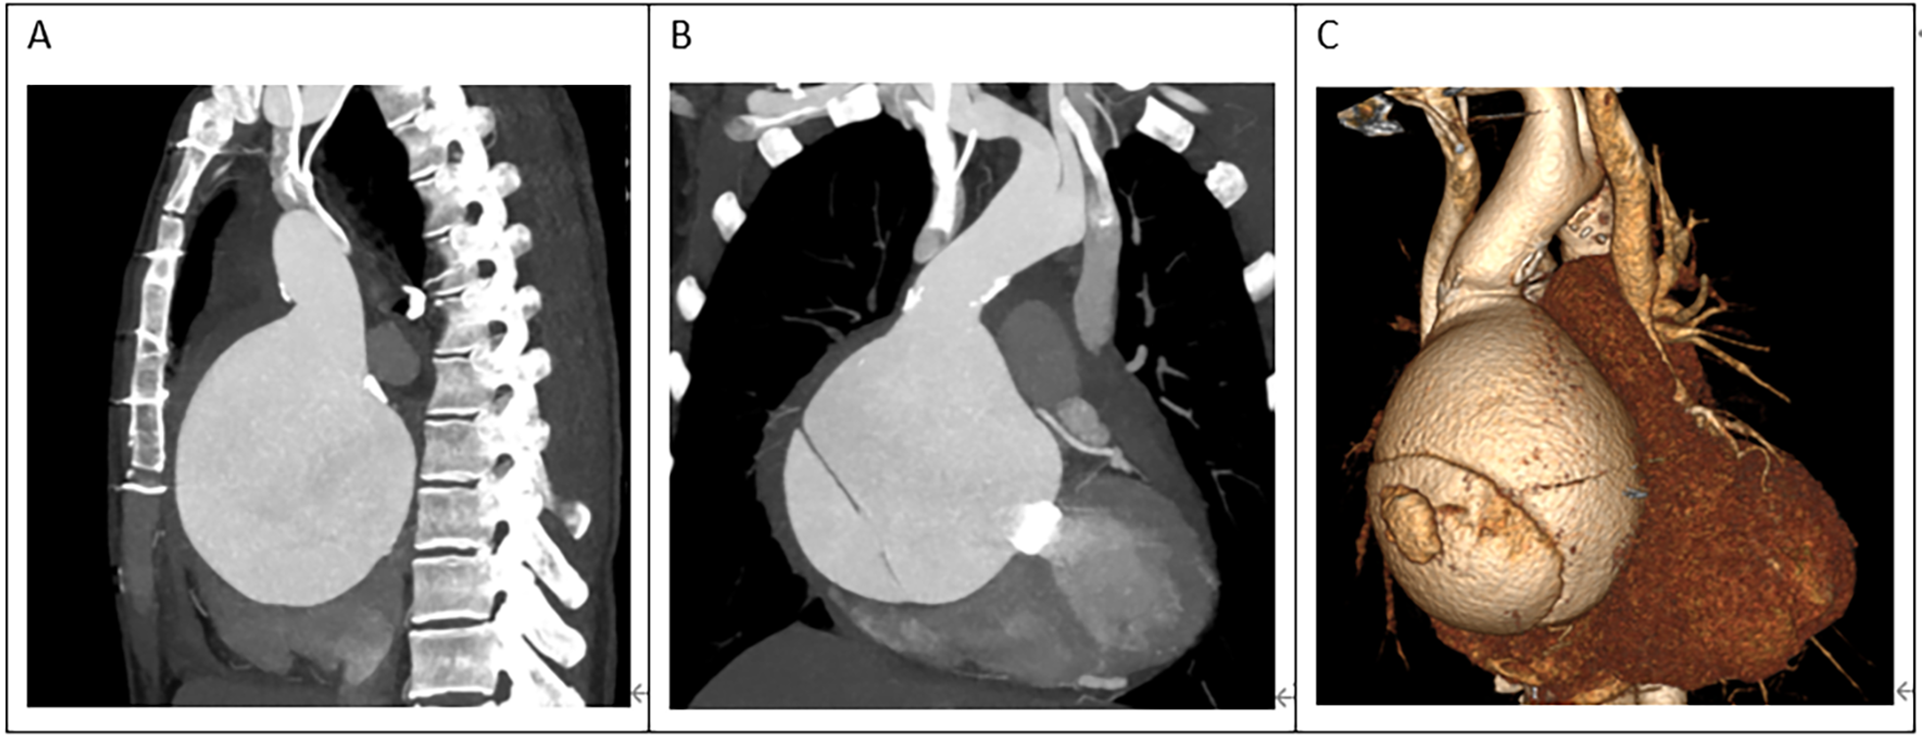

A 45-year-old female patient, with a height of 155 cm and a low weight of 42 kg, was admitted to the hospital due to severe chest and back pain that had persisted for 9 h. The patient had undergone mechanical aortic valve replacement and aortic arch coarctation repair at our hospital 20 years earlier (the two operations were performed concomitantly). She had been taking warfarin for long time. She rarely received follow-up after surgery. Upon admission, the patient exhibited significant pain symptoms, accompanied by chest tightness, shortness of breath, and difficulty breathing; however, her vital signs were relatively stable, with a heart rate of 90–100 beats per minute. The physical examination revealed obvious surgical scars on the chest and left side of the thorax. Mechanical valve opening and closing sounds could be heard in the precordial area, along with a 3/6 grade systolic murmur. The electrocardiogram showed sinus rhythm, regular rhythm, and complete right bundle branch block. Echocardiography revealed a giant ascending aortic dissection aneurysm. The mean pressure gradient across the original mechanical aortic valve was 30 mmHg, with a peak gradient of 56 mmHg. The left ventricular diameter was 40 mm, the left atrial diameter was 19 mm, and the left ventricular ejection fraction (LVEF) was 70%. The enhanced computed tomography angiography (CTA) scan supported the presence of a giant ascending aortic dissecting aneurysm, with the largest cross-sectional area measuring approximately 101.3 × 85.2 mm (Figure 1). Contrast medium was observed to leak from the false lumen (Figure 1). The patient was slender, and the aneurysm occupied almost the entire anterior and posterior mediastinum (Figure 2A), severely compressing the heart (Figures 2B,C).

Figure 1

A giant aortic dissecting aneurysm. Contrast medium was observed to leak from the false lumen (red arrow).

(A) The ascending aortic aneurysm was extremely large, occupying almost the entire mediastinum. (B,C) The heart was severely compressed.